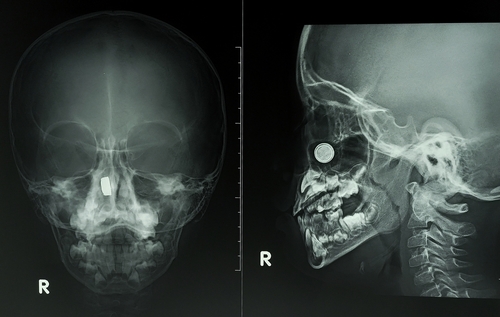

Чаще всего, протокол исследования включает в себя описание следующих тонкостей рентгена носоглотки в норме:

- Наличие переломов и деформаций носовой кости.

- Образования округлой формы, расположенные у стенок синуса вблизи носовых пазух, определяющиеся как кисты. Новообразования на рентгенограмме носоглотки визуализируются как тени с нечетким контуром.

- Описанию поддаются миндалины, так как при просвете носоглотки хорошо видно степень гипертрофии и общее состояние аденоидов.